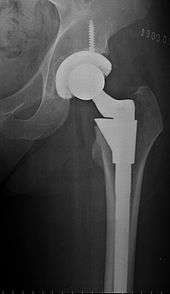

Hip replacement is a surgical procedure in which the hip joint is replaced by a prosthetic implant. Hip replacement surgery can be performed as a total replacement or a hemi (half) replacement. Such joint replacement orthopaedic surgery is generally conducted to relieve arthritis pain or in some hip fractures. A total hip replacement (total hip arthroplasty) consists of replacing both the acetabulum and the femoral head while hemiarthroplasty generally only replaces the femoral head. Hip replacement is currently the most common orthopaedic operation, though patient satisfaction short- and long-term varies widely. The average cost of a total hip replacement in 2012 was $40,364 in the United States, and about $7,700 to $12,000 in most European countries.[1]

Implants

The prosthetic implant used in hip replacement consists of three parts: the acetabular cup, the femoral component, and the articular interface. Options exist for different people and indications. The evidence for a number of newer devices is not very good, including: ceramic-on-ceramic bearings, modular femoral necks, and uncemented monoblock cups.[15] Correct selection of the prosthesis is important.

Acetabular cup

The acetabular cup is the component which is placed into the acetabulum (hip socket). Cartilage and bone are removed from the acetabulum and the acetabular cup is attached using friction or cement. Some acetabular cups are one piece, while others are modular. One-piece (monobloc) shells are either UHMWPE (ultra-high-molecular-weight polyethylene) or metal, they have their articular surface machined on the inside surface of the cup and do not rely on a locking mechanism to hold a liner in place. A monobloc polyethylene cup is cemented in place while a metal cup is held in place by a metal coating on the outside of the cup. Modular cups consist of two pieces, a shell and liner. The shell is made of metal; the outside has a porous coating while the inside contains a locking mechanism designed to accept a liner. Two types of porous coating used to form a friction fit are sintered beads and a foam metal design to mimic the trabeculae of cancellous bone and initial stability is influenced by under-reaming and insertion force.[16] Permanent fixation is achieved as bone grows onto or into the porous coating. Screws can be used to lag the shell to the bone providing even more fixation. Polyethylene liners are placed into the shell and connected by a rim locking mechanism; ceramic and metal liners are attached with a Morse taper.

Femoral component

The femoral component is the component that fits in the femur (thigh bone). Bone is removed and the femur is shaped to accept the femoral stem with attached prosthetic femoral head (ball). There are two types of fixation: cemented and uncemented. Cemented stems use acrylic bone cement to form a mantle between the stem and to the bone. Uncemented stems use friction, shape and surface coatings to stimulate bone to remodel and bond to the implant. Stems are made of multiple materials (titanium, cobalt chromium, stainless steel, and polymer composites) and they can be monolithic or modular. Modular components consist of different head dimensions and/or modular neck orientations; these attach via a taper similar to a Morse taper. These options allow for variability in leg length, offset and version. Femoral heads are made of metal or ceramic material. Metal heads, made of cobalt chromium for hardness, are machined to size and then polished to reduce wear of the socket liner. Ceramic heads are more smooth than polished metal heads, have a lower coefficient of friction than a cobalt chrome head, and in theory will wear down the socket liner more slowly. As of early 2011, follow-up studies in patients have not demonstrated significant reductions in wear rates between the various types of femoral heads on the market. Ceramic implants are more brittle and may break after being implanted.